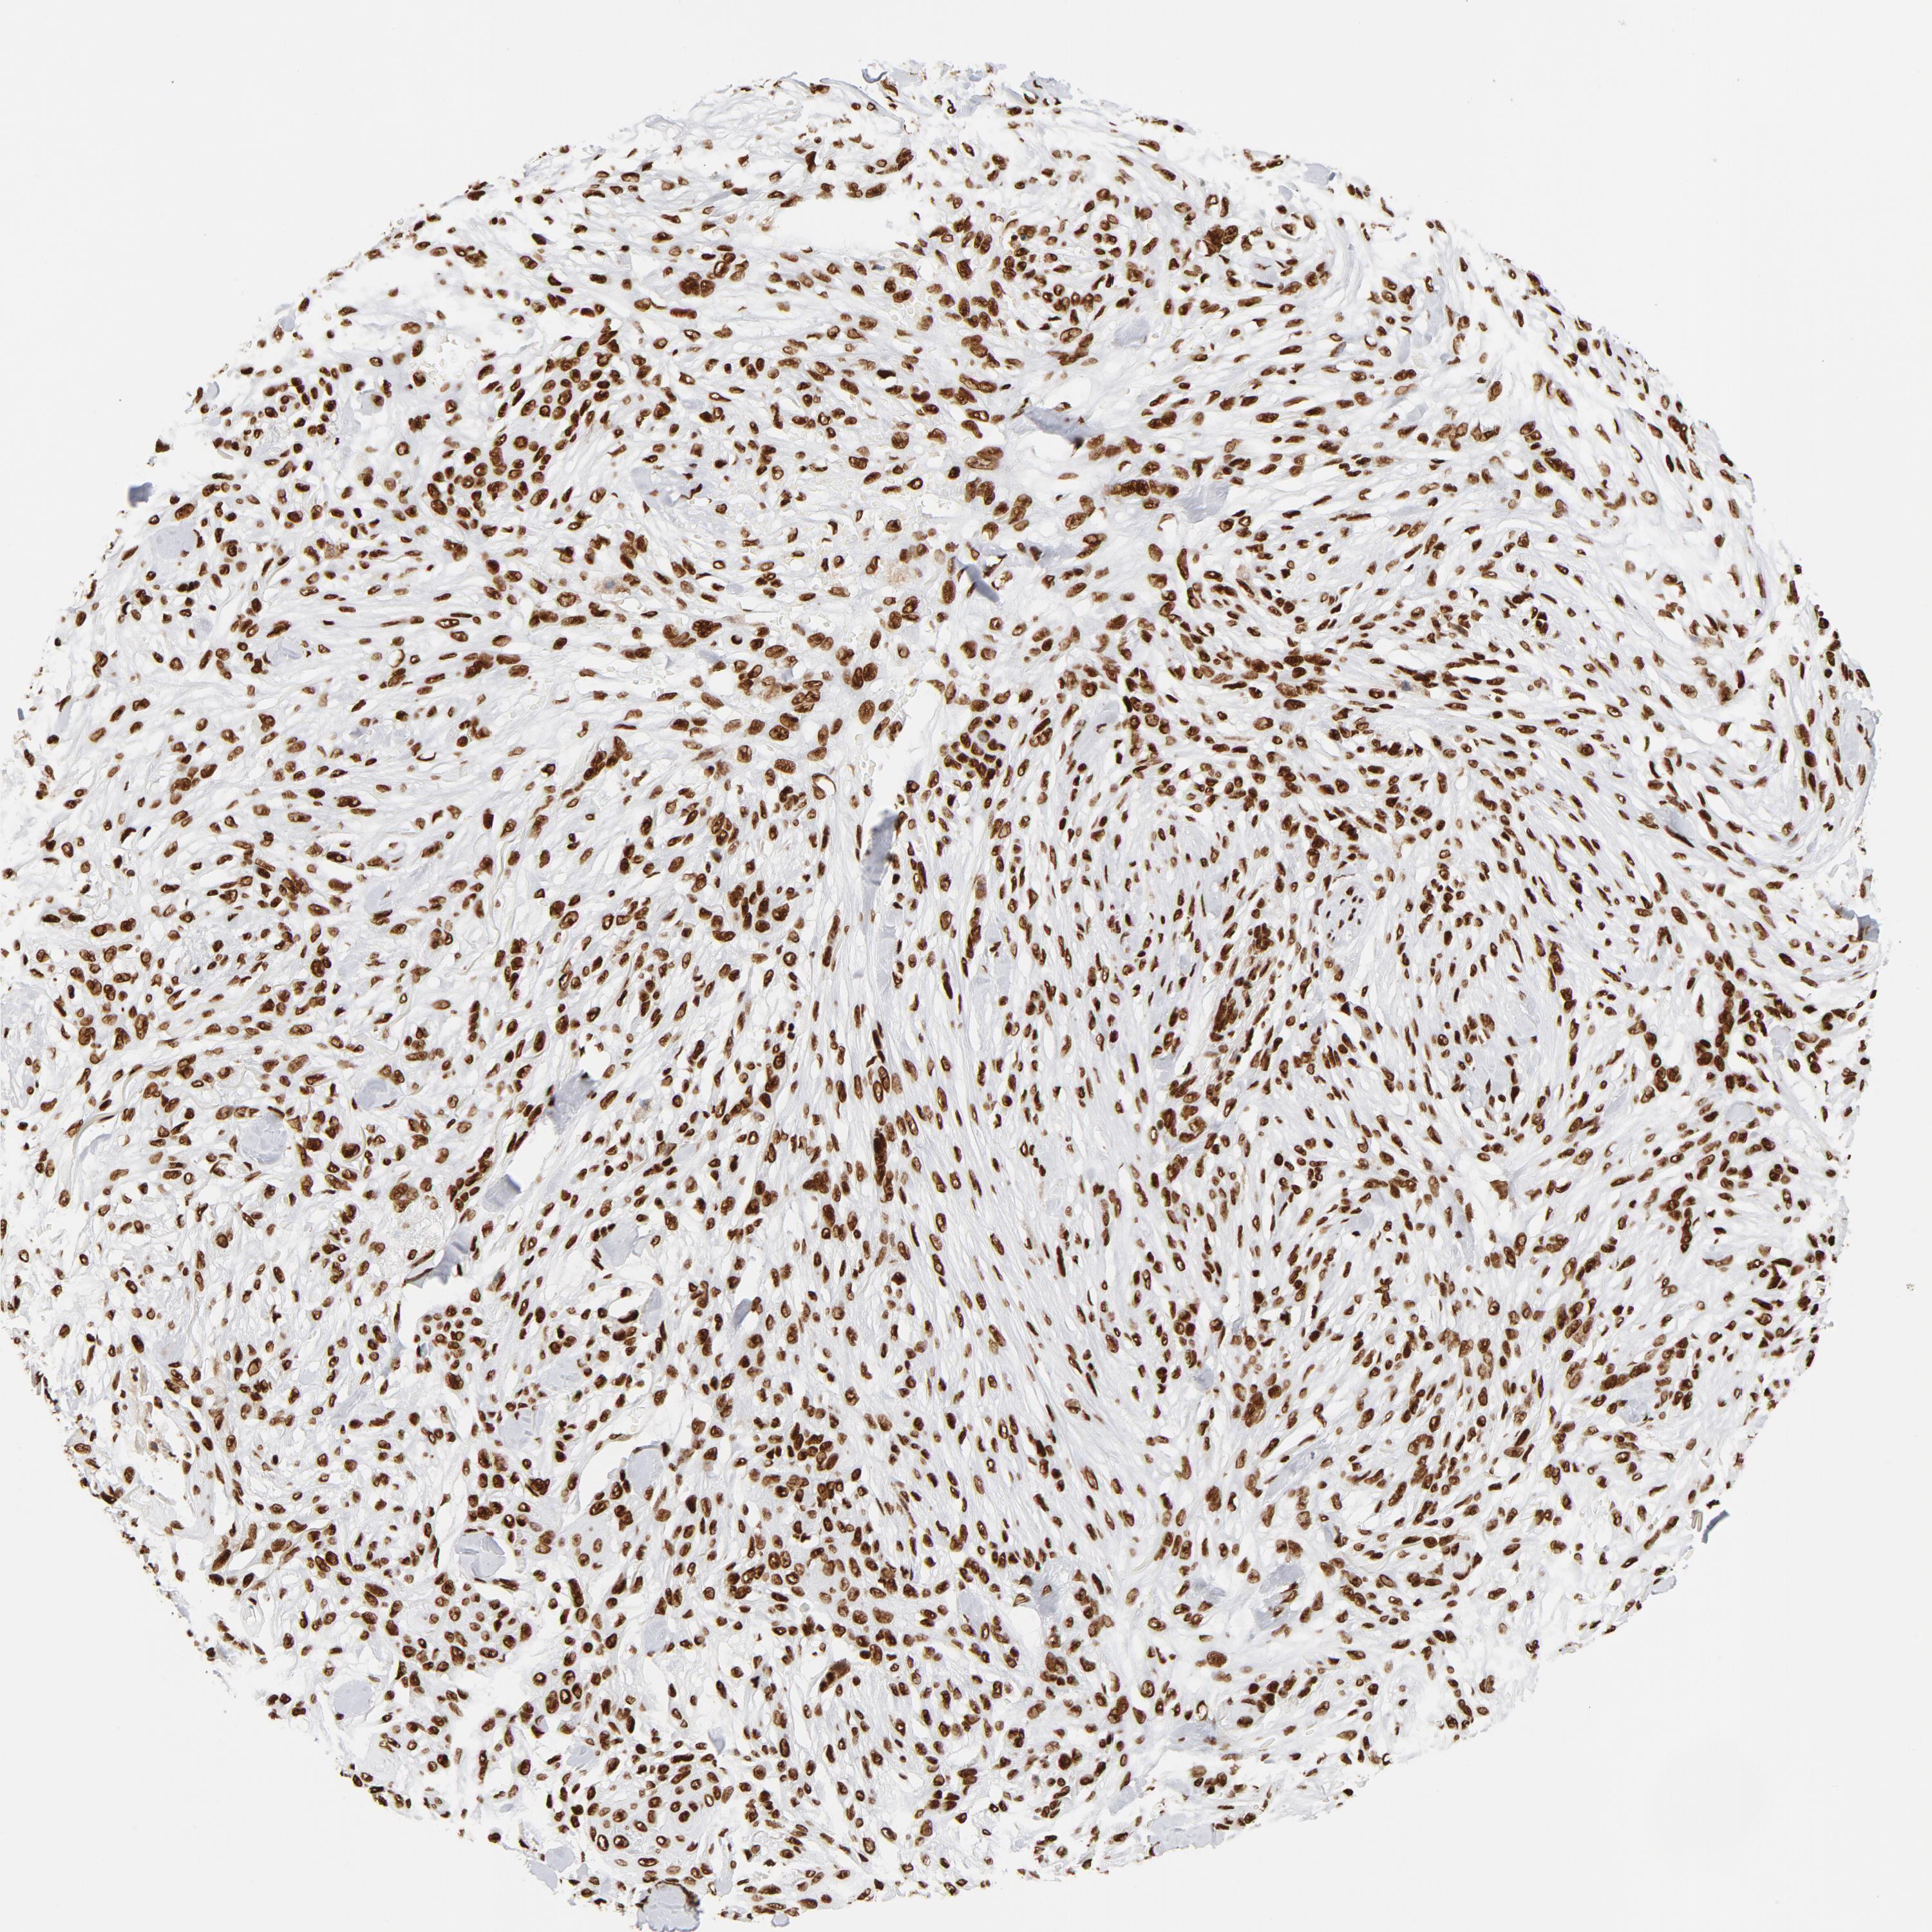

SKIN CANCER - Protein expressioni

A mouse-over function shows sample information and annotation data. Click on an image to view it in a full screen mode. Samples can be filtered based on level of antibody staining by selecting one or several of the following categories: high, medium, low and not detected. The assay and annotation is described here.

Antibody stainingi

Antibody staining in the annotated cell types in the current human tissue is reported as not detected, low, medium, or high, based on conventional immunohistochemistry profiling in selected tissues. This score is based on the combination of the staining intensity and fraction of stained cells.

Each image is clickable and will lead to virtual microscopy that enables deeper exploration of all samples and also displays staining intensity scores, fraction scores and subcellular localization as well as patient and tissue information for each sample.

Antibody HPA047549

Antibody HPA062226

Antibody CAB004254

Staining

High

Medium

Low

Not detected

Intensity

Strong

Moderate

Weak

Negative

Quantity

>75%

75%-25%

<25%

None

Location

Nuclear

Cytoplasmic/membranous

Cytoplasmic/membranous,nuclear

Squamous cell carcinoma, NOS

Squamous cell carcinoma, metastatic, NOS

Basal cell carcinoma